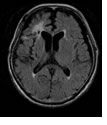

| 図①:正常のMRI画像。 |

図②:脳梗塞が右半球

に観られます。 |